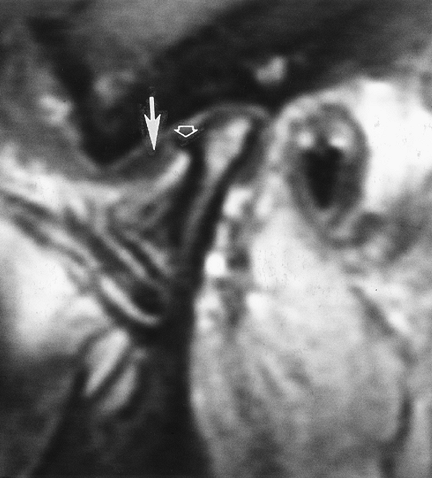

![]() |

FIGURE 2-6 Posttraumatic arthritis with narrowing on the right (A) and an osteochondral defect (arrow) and subluxation on the left (B).

FIGURE 2-7 Osteoarthritis and internal derangement on sagittal (A), axial (B), and coronal (C) computed tomography images. There is joint space narrowing and asymmetry with osteophyte formation.

FIGURE 2-8 Sagittal T1-weighted MR image with anterior disc displacement (arrow) and a condylar osteophyte (open arrow).